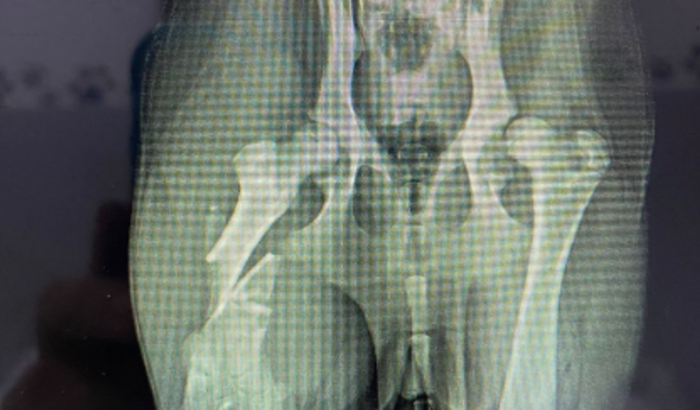

bom, me chamo Eliane, recentemente adotei uma cachorrinha chamada Kiara, a uns dias atras a kiara foi atropelada e infelizmente a pessoa não parou pra ajudar, estou fazendo essa vakinha, pois não consigo arcar com o valor, a kiara vai ter que fazer uma cirurgia no osso do fêmur, e se não fizer, corre risco de amputar a perna ou até perde a vida, então venho aqui pedir pra que vocês me ajudem nessa!!